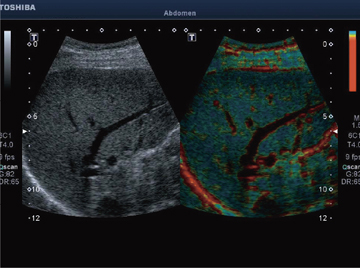

Realtime Application Platformとは,高速リアルタイム処理を実現し新アプリケーションを可能とするプラットフォームである。Elastographyをはじめ,びまん性肝疾患の評価に期待される当社独自のASQ(Acoustic Structure Quantification)をリアルタイム化(図4,5)。また,エコー像とCT像/MRI像を連動させ,病変の検出および治療支援に有効な"Smart Fusion"に対応している(図6)。このSmart Fusionは,通常のコンベックスプローブ以外にマイクロコンベックスプローブ,穿刺用コンベックスプローブにも対応しているため,早期発見から治療までを幅広くサポートする(図7)。また,磁気送信機は装置一体型のアームに取り付けるため,省スペースで移動も楽に行える(図8)。これらの機能により,病変の検出および質的診断に期待が持たれている。

![]() 図5 ASQ(正常肝) |